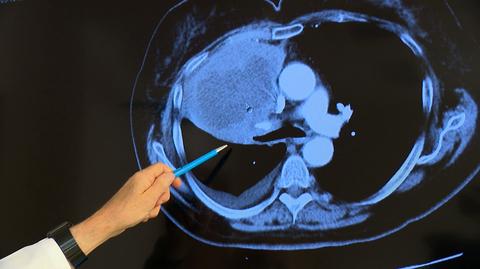

Lekarze apelują i zachęcają, by zgłaszać się do programu wczesnego wykrywania raka płuc. Program właśnie rusza. Pacjentów nie brakuje, ale trzeba przezwyciężyć lęk przed COVID-em, albo wykazać się cierpliwością i determinacją w walce z systemem.

Antybiotyk jednak na guz nowotworowy w płucach nie pomógł, bo pomóc nie mógł. Pacjentka ponownie w sierpniu zgłosiła się do lekarza podstawowej opieki zdrowotnej. Tym razem lekarz przepisuje pani Teresie środki przeciwbólowe. Te na nowotwór też nie pomagają. W ciągu pięciu miesięcy pacjentkę z nowotworem płuc trzy razy przyjmują lekarze POZ. Trzy razy przez telefon. Nie badają i nie kierują na żadne badania, nawet na zwykłe prześwietlenie.

Zdesperowana pani Teresa ostatecznie bez skierowania poszła do pulmonologa, który wreszcie skierował ją na badania. Profesor Tadeusz Orłowski przyznaje, że w przypadku pani Teresy stracony został bardzo cenny czas.

- Jednak między kwietniem a październikiem czy wrześniem, kiedy chora się zgłosiła do nas, minęło prawie pół roku. Wydaje nam się, że leczenie byłoby bardziej skuteczne, gdyby było rozpoczęte w kwietniu - uważa profesor Tadeusz Orłowski z Instytutu Gruźlicy i Chorób Płuc.